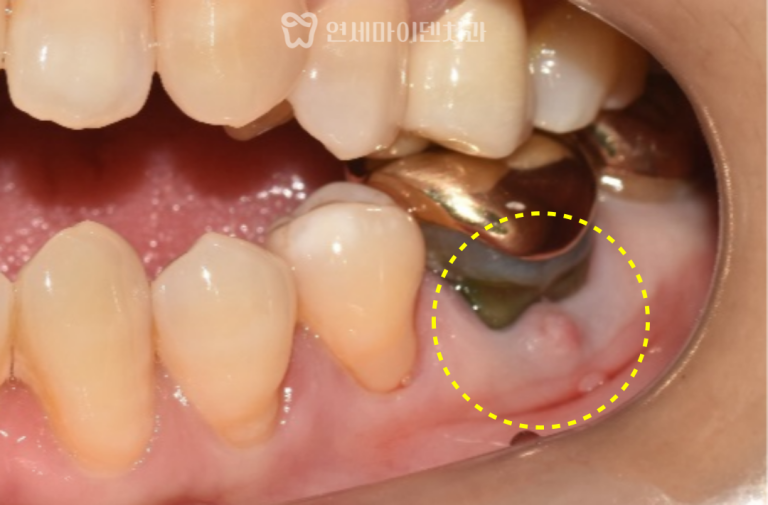

26번 치아 — 발치 즉시 임플란트

그러나 바로 뒤쪽의 #26번 치아는 상황이 달랐습니다.

보철물을 제거하자 내부에서 출혈이 계속되어 CT를 재확인했더니

구개측 뿌리(perforation)가 뚫린 상태였습니다.

염증으로 인해 주변 뼈 손실이 심했고,

이미 MTA(특수 치근 수복재)를 적용하기엔

시기를 놓친 상태였습니다.

임플란트 식립 한 달만에

식립 부위가 깨끗하게 아무는 것을 확인할 수 있습니다.